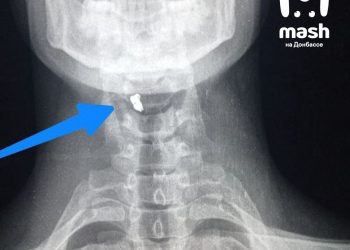

Боец в ЛНР выжил после ранения осколком в шею

Наш военнослужащий получил серьезное ранение осколком в шею, но несмотря на это сумел выжить, пишет Mash. Доброволец был ранен при ...